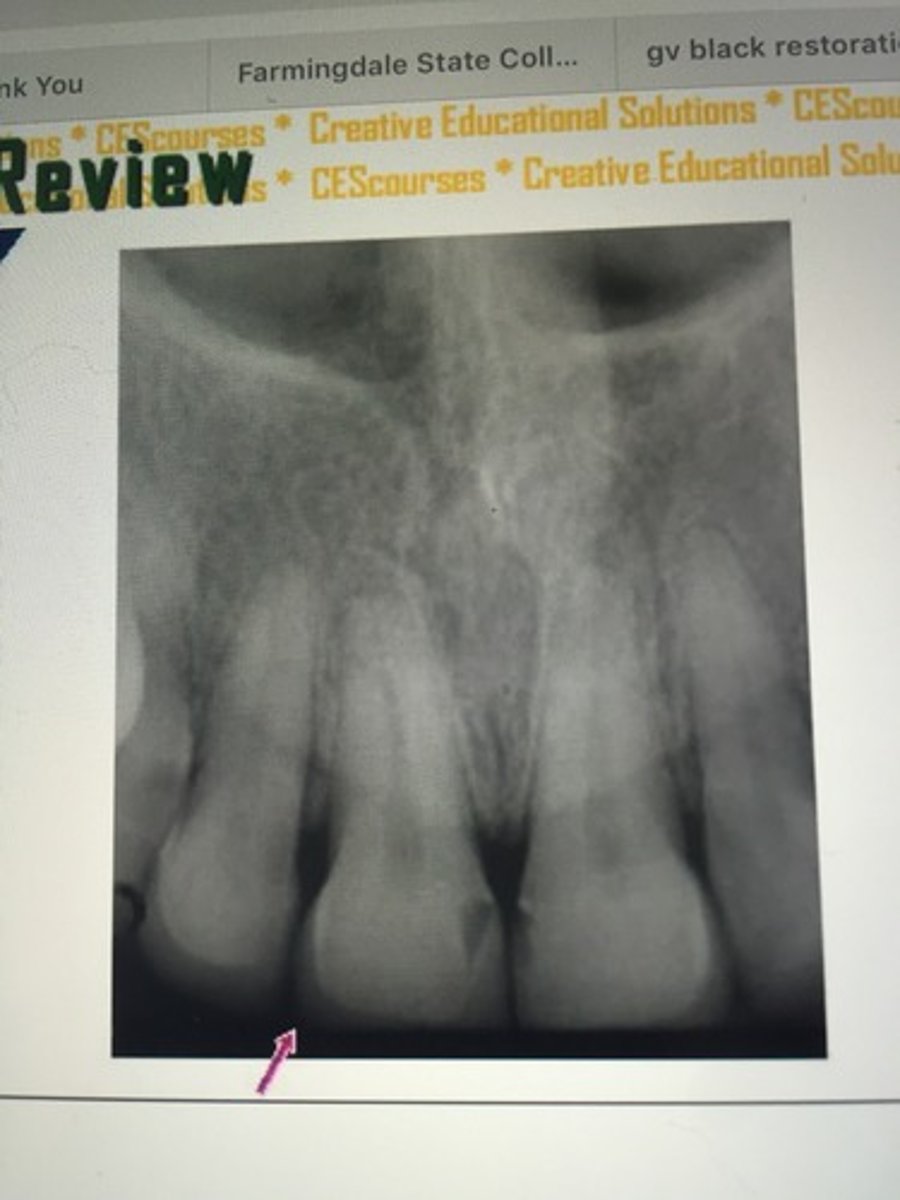

decay

gold crown

porcelain crown

gold crown with post